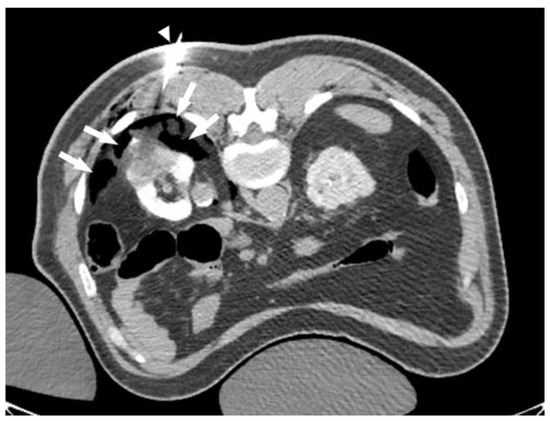

Figure 2. CO2 dissection. CT scan of the same patient in Figure 1 during ablation. CO2 has been injected through a 21 g needle (white triangle). Notice that CO2 (arrows) accumulates in the most posterior, non-dependent, fat planes, creating an insulating plane between the kidney and intercostal nerves.

Another safety consideration is the proximity of exophytic lesions to the surrounding organs, including the genitofemoral nerve, along the psoas muscle, the intercostal nerves, and the adjacent viscera, including the colon, liver, and spleen. We almost always use dissection techniques (using 20–21 G needles) to protect these structures. We recommend using CO2 dissection to protect the posterior structures (Figure 2). For dependent structures, such as the colon and liver, we may use normal saline to hydro-dissect these structures away from the ablation zone.

The ablation of RCCs > 4 cm can be technically challenging; however, it is very rewarding, especially in non-surgically fit patients. There are two main factors that have to be considered when ablating large RCCs. The first consideration is safety. The ablation of large RCCs requires the formation of a large ice ball, which may carry a risk of accidental injury to the surrounding organs. A review of the pre-procedure CT/MRI scan is essential to predict potential threats to nearby organs and plan accordingly. In our experience, dissection techniques, using CO2 or normal saline, are very effective in this context. We prefer CO2 dissection to protect the posterior structures, such as intercostal nerves. When patients are in a prone position, CO2 accumulates in the non-dependent fat planes, which provide excellent protection for the posterior structures (Figure 2). For RCCs close to the collecting system, pyeloperfusion using the protocol described has been very helpful to minimize trauma to the ureter and renal pelvis. Patients may develop mild self-limited hematuria following ablation; however, we did not experience more serious complications, such as urine leaks or ureteric strictures. In our experience, cryoablation is safe when performed adjacent to the renal vasculature, but careful attention is needed during the advancement of the probes to avoid direct injury to the hilar vessels. In general, using multiple probes increases the risk of bleeding, given the hypervascular nature of most RCCs. In addition, careful spacing and alignment of the probes are needed to ensure uniform ice ball formation, especially when ablation is close to the renal hilum. Of note, post-procedural bleeding and perinephric hematoma are common with cryoablation. Most of these hematomas are self-limited and do not require further intervention. If there is clinical concern, we admit patients overnight for the observation and monitoring of hemoglobin and hematocrit values every 8 hours. If there is concern about active bleeding, we have a low threshold for performing a renal angiogram and embolization of the bleeding source.